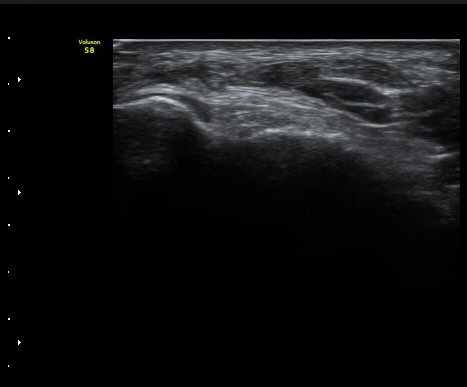

¹ß¸ñ°üÀý Á¾´Ü¸é°Ë»ç¿¡¼­ °üÀý³» ¼ö¾×Àú·ù°¡ °üÂûµÈ´Ù(±×¸² 1).

±×¸²1) ¹ß¸ñ°üÀý Á¾´Ü¸é°Ë»ç±Û